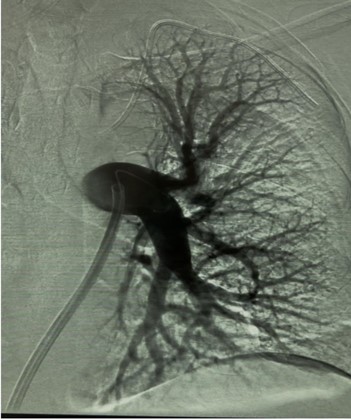

Usually, access was gained in the right femoral vein, and a 16-F, 65-cm Gore DrySeal sheath (Gore & Associates) was introduced into the vasculature and placed in the right or left main pulmonary artery (PA). A Lightning Flash HTORQ was then advanced into the right main PA. To place Lightning Flash into the correct anatomy, the catheter was deftly tracked over a 6-F Select Catheter (Penumbra, Inc.) with a Bernstein tip shape and a 0.035-inch Amplatz guidewire (Boston Scientific Corporation). With the catheter in place, aspiration was initiated. In 2.5 minutes of device time, the thrombus burden was extracted from the right or left main PA (Figure 1), and pulmonary angiography displayed considerable improvement from the beginning of the case (Figure 2).

Figure 1: Thrombus burden was extracted from the left main pulmonary artery